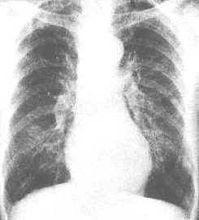

慢性喘息型支氣管炎慢性喘息型支氣管炎的發病年齡較晚,家屬史和過敏史不顯著,先有咳嗽及咳痰,以後才發展為喘息症狀,在秋冬季節或感冒時症狀加重,咳嗽、咳痰及喘息遷延不愈,早晚咳嗽;呼氣延長,有時肺底部可聽到濕性羅音或哮鳴音,套用支氣管擴張藥後肺功能改善不明顯。而支氣管哮喘病人則常自幼得病,有明顯的家屬史和過敏史,無慢性咳嗽、咳痰史,季節性強,哮喘突然發作,突然緩解,間歇期間可無症狀,不咳痰,發作時肺部滿布哮鳴音,間歇期間肺部的呼吸音可以正常,套用支氣管擴張藥後肺功能可得到改善。